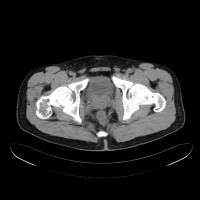

常发生于5到15岁的儿童,男性发病多于女性,比率约为2:1。病变部位多在长骨干骺端。最常见部位为肱骨近端,其次为股骨近端。活动性(active相对具有侵袭性的)骨囊肿靠近骨骺区,随着儿童年龄增大,病灶会逐渐远离骨骺,成为非活动性(inactive)。在年龄超过17岁的患者,病变会在非长管骨发生,如跟骨骨盆等。

有经验的骨肿瘤医生仅凭X线平片就可以作出骨囊肿的临床诊断。病变灶为边界清晰的液性低密度灶,四壁为薄层的硬化灶壳。病变灶略向近骨骺的干骺部位扩大。病灶非偏心性,也不破坏骨外壳,更不会突破骨质形成骨膜外反应骨,除非是在病理骨折后的愈合期。有时脱落的骨皮质成份落入囊腔中,X片显示被称为“落叶征”(FallenleaforFallenfragment)。当病灶发生在骨盆,CT扫描对病灶部位及囊肿形态的判断有价值。MRI可以明确囊内富含的液性成分。骨ECT扫描表现为外周薄的浓集而中央病灶冷区。

二CT:

1.骨囊肿一般多呈圆形、卵圆形低密度骨质缺损,边缘清晰,无硬化。

2.局部骨皮质变薄呈囊性膨胀。

3.少数囊肿内可见骨性间隔,呈多房改变。

4.骨囊肿内的CT值多为水样密度,有出血时密度可升高。

5.增强扫描囊肿不强化。